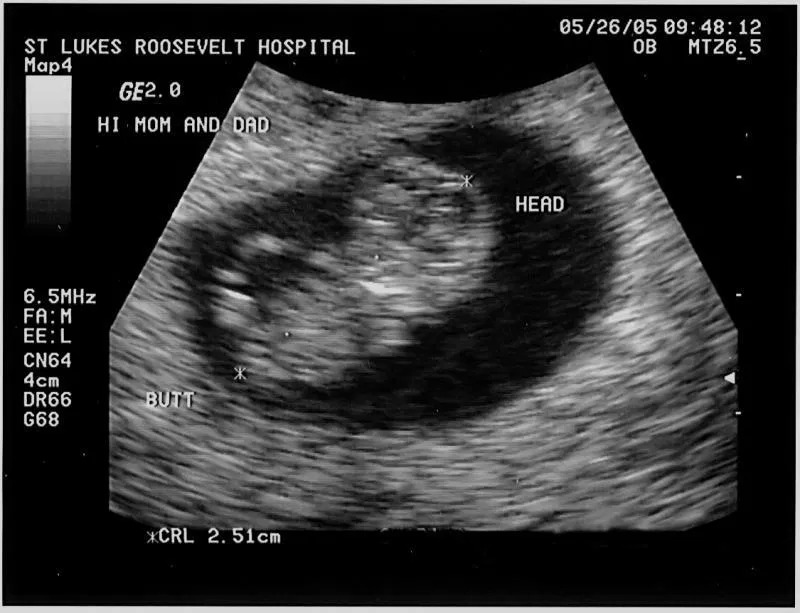

Tuần thứ 9 là khoảng thời gian quan trọng, đánh dấu bước phát triển mới của thai nhi. Đây cũng là lúc tim thai đã hoạt động tương đối ổn định nên siêu âm trong giai đoạn này sẽ dò được tim thai, thu nhận các chỉ số về sức khỏe để xác định mức độ phát triển của bé, đồng thời phát hiện bệnh lý nếu có.

Tại thời điểm này, việc lựa chọn hình thức siêu âm đóng vai trò quan trọng, quyết định đến tính chính xác của hoạt động kiểm tra. Có hai hình thức siêu âm thịnh hành hiện nay, đó là siêu âm bụng và siêu âm đầu dò. Theo các bác sĩ chuyên khoa, khi mang thai ở tuần thứ 9, mẹ nên lựa chọn hình thức siêu âm đầu dò để dễ can thiệp sâu, giúp lấy dữ liệu và các chỉ số chính xác hơn.

Khi thực hiện siêu âm ở tuần 9, mẹ không chỉ nhận thông tin về chỉ số sức khỏe và mức độ phát triển của thai nhi mà còn có thể theo dõi hình dáng, nhịp tim thai và quá trình hình thành của các hệ cơ quan khác. Thai nhi 9 tuần tuổi nhìn chung đã phát triển tương đối hoàn chỉnh về tim thai, khớp hàm và các đốt xương khớp cơ bản cũng như mao mạch trên cơ thể. Vì vậy, mẹ cần đi siêu âm để kiểm tra tim thai, túi thai, phòng tránh tình trạng sảy thai hoặc bị ít nước ối.

Chiều dài đầu mông (CRL) từ 23 - 30 mm

Tim thai 9 tuần tuổi có nhịp đập trung bình 170 nhịp/phút, hệ thống tĩnh mạch và động mạch hình thành tương đối hoàn chỉnh.